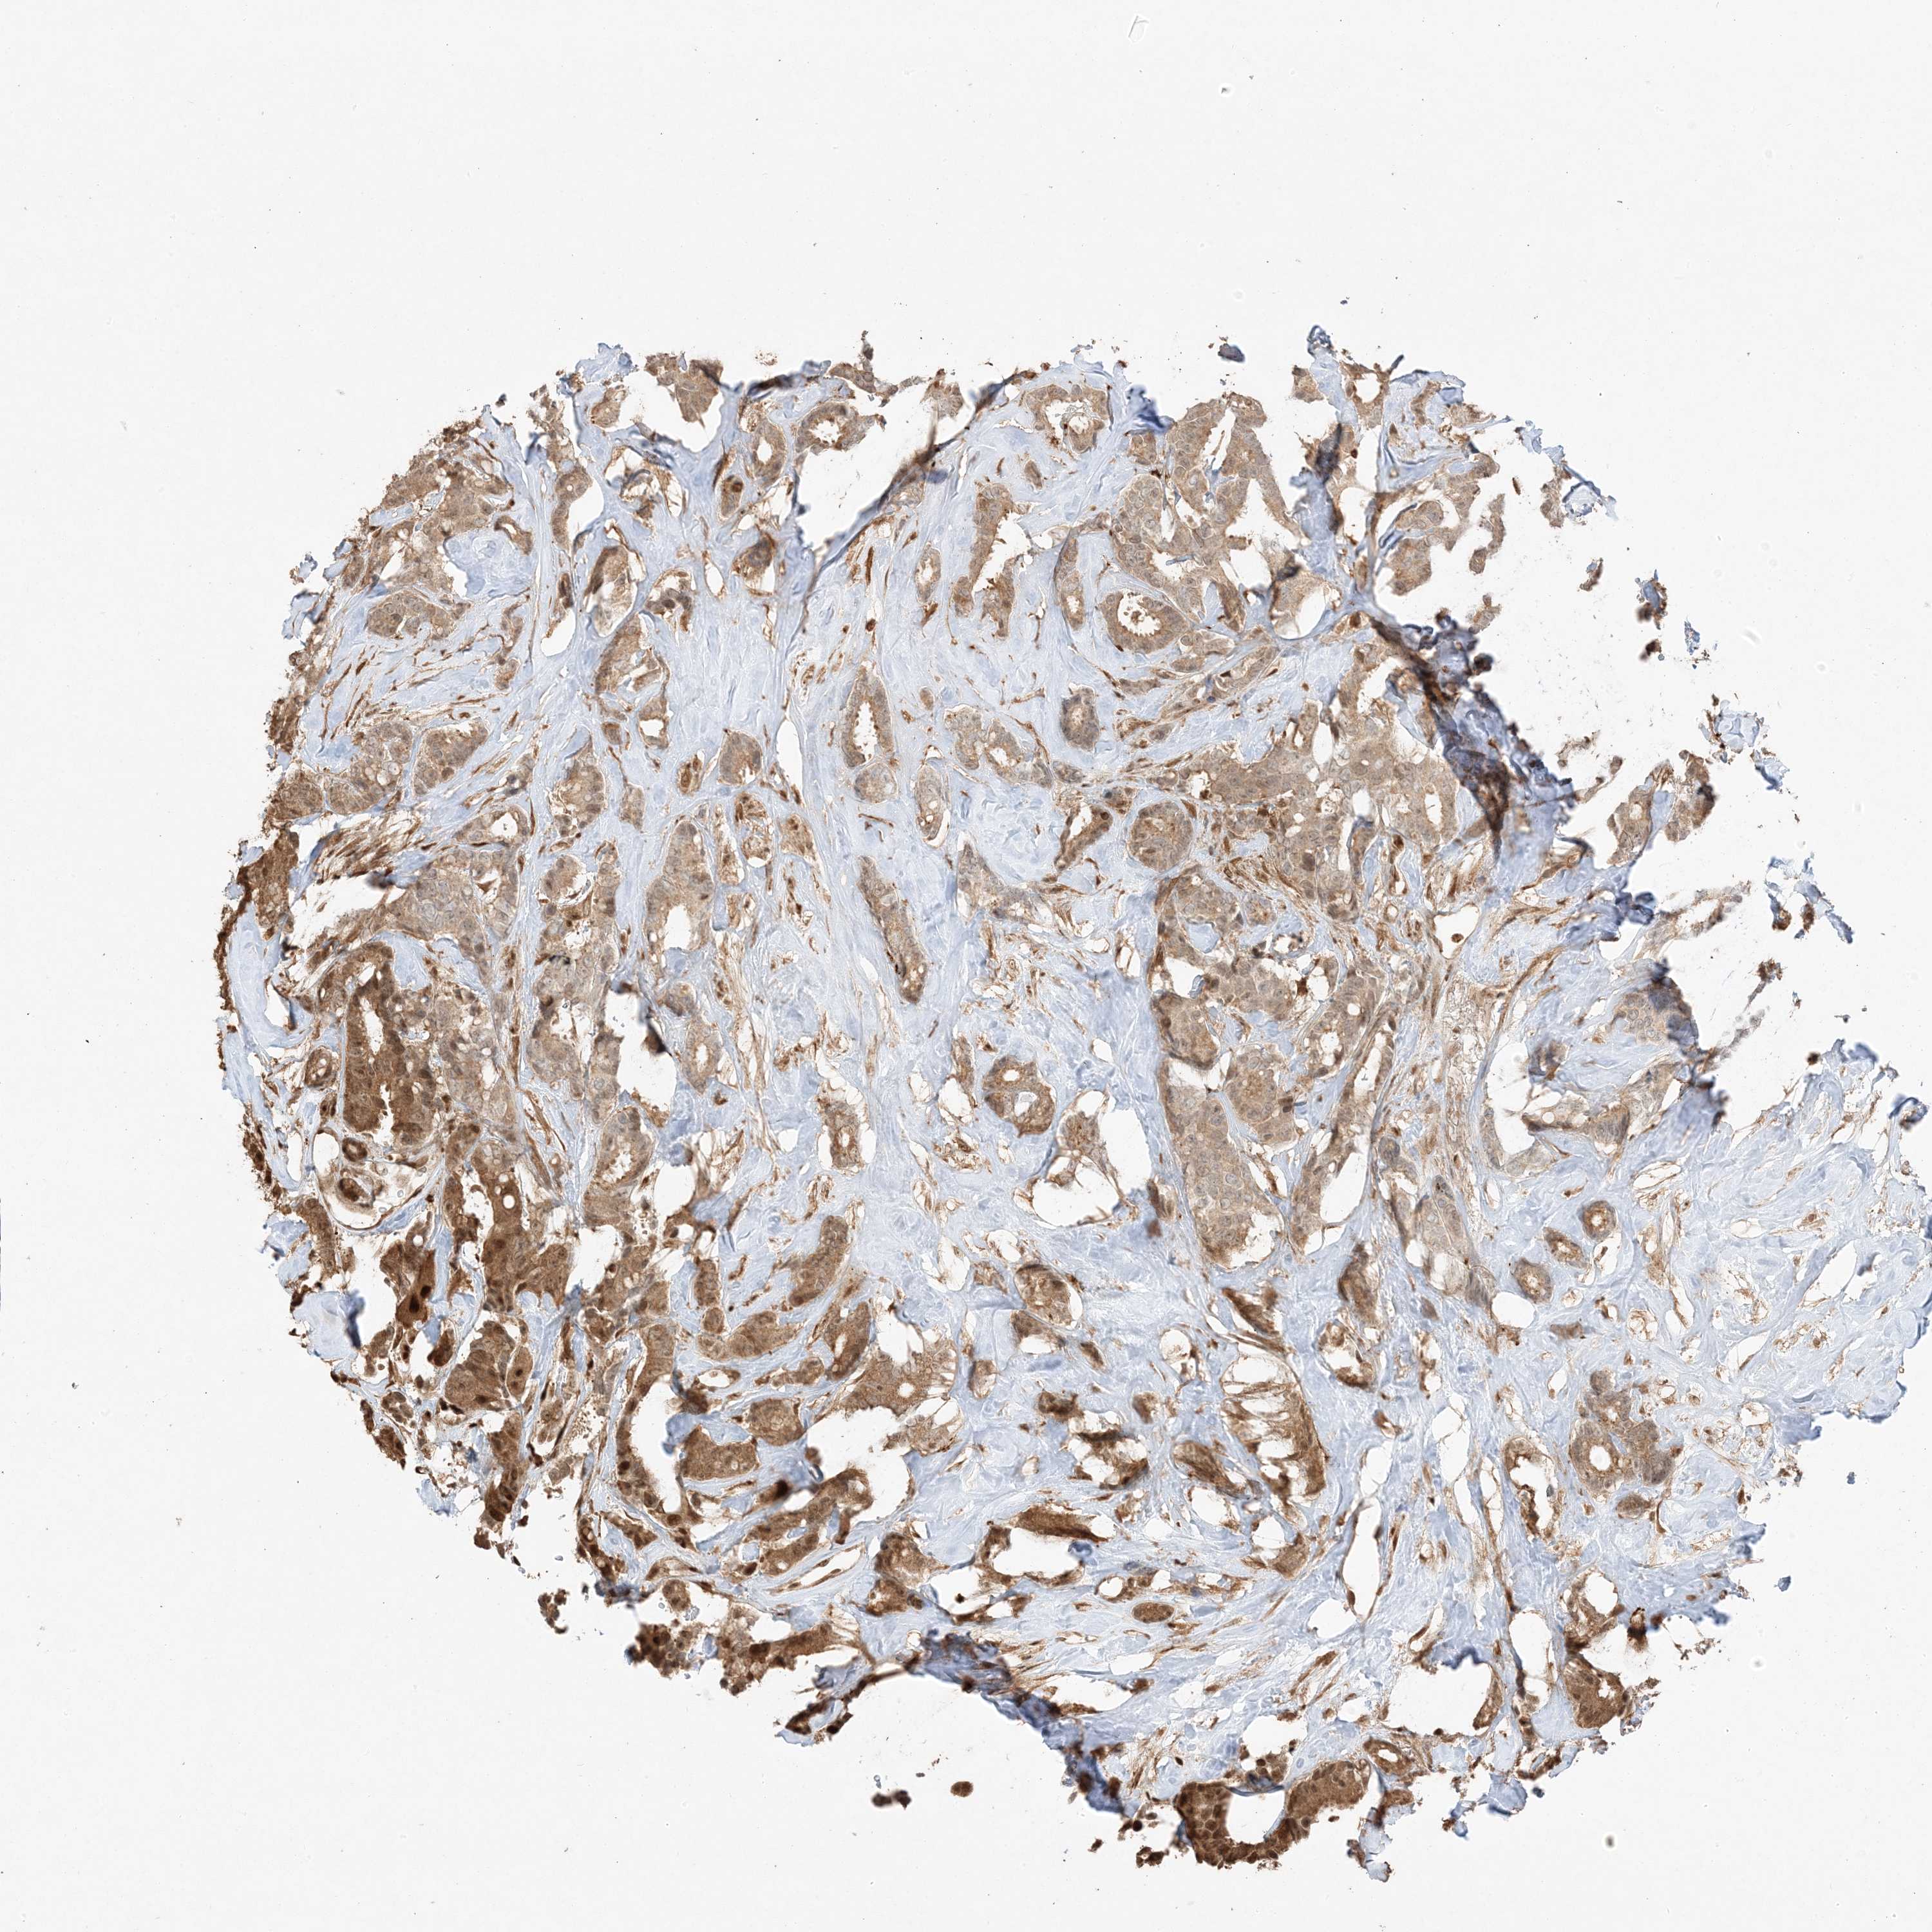

CANCER BREAST CANCER Show tissue menu

BRCA TCGA BRCA VALIDATION PROTEIN EXPRESSION